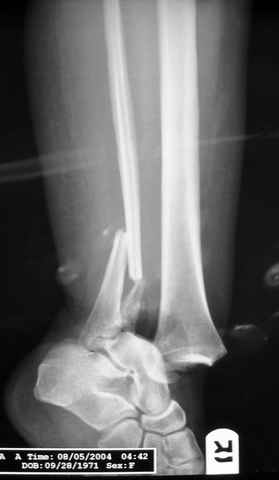

Re: ANKLE FRACTURE